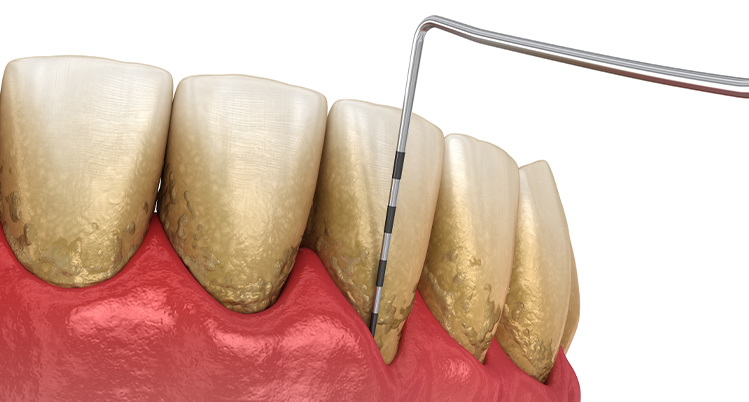

1. 歯周ポケットの深さを測定

専用の器具を使って歯ぐきの深さを測る検査です。定期健診などで行っている歯ぐきの検査と同じです。歯ぐきの深さを測るため少しチクチクと痛みを感じる方もいます。

1本の歯につき4~6か所測定します。

• 0~3mm 正常、歯肉炎、または軽度

• 4~6mm 中等度歯周炎

• 7mm以上 重度歯周炎